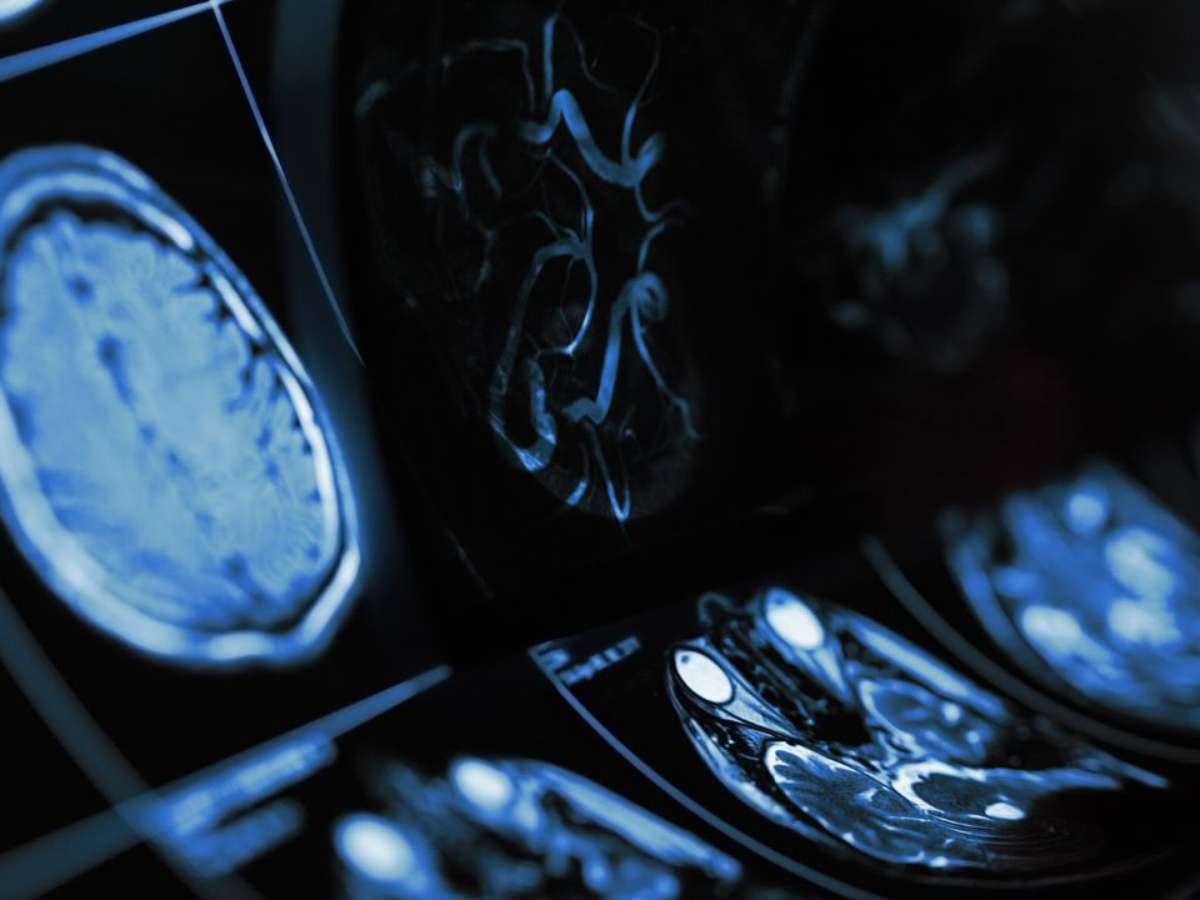

AVC é uma das principais causas de morte no Brasil; veja como reconhecer os sinais e adotar hábitos que ajudam a prevenir

Foto: Reprodução: Canva/Yuriy / Bons Fluidos